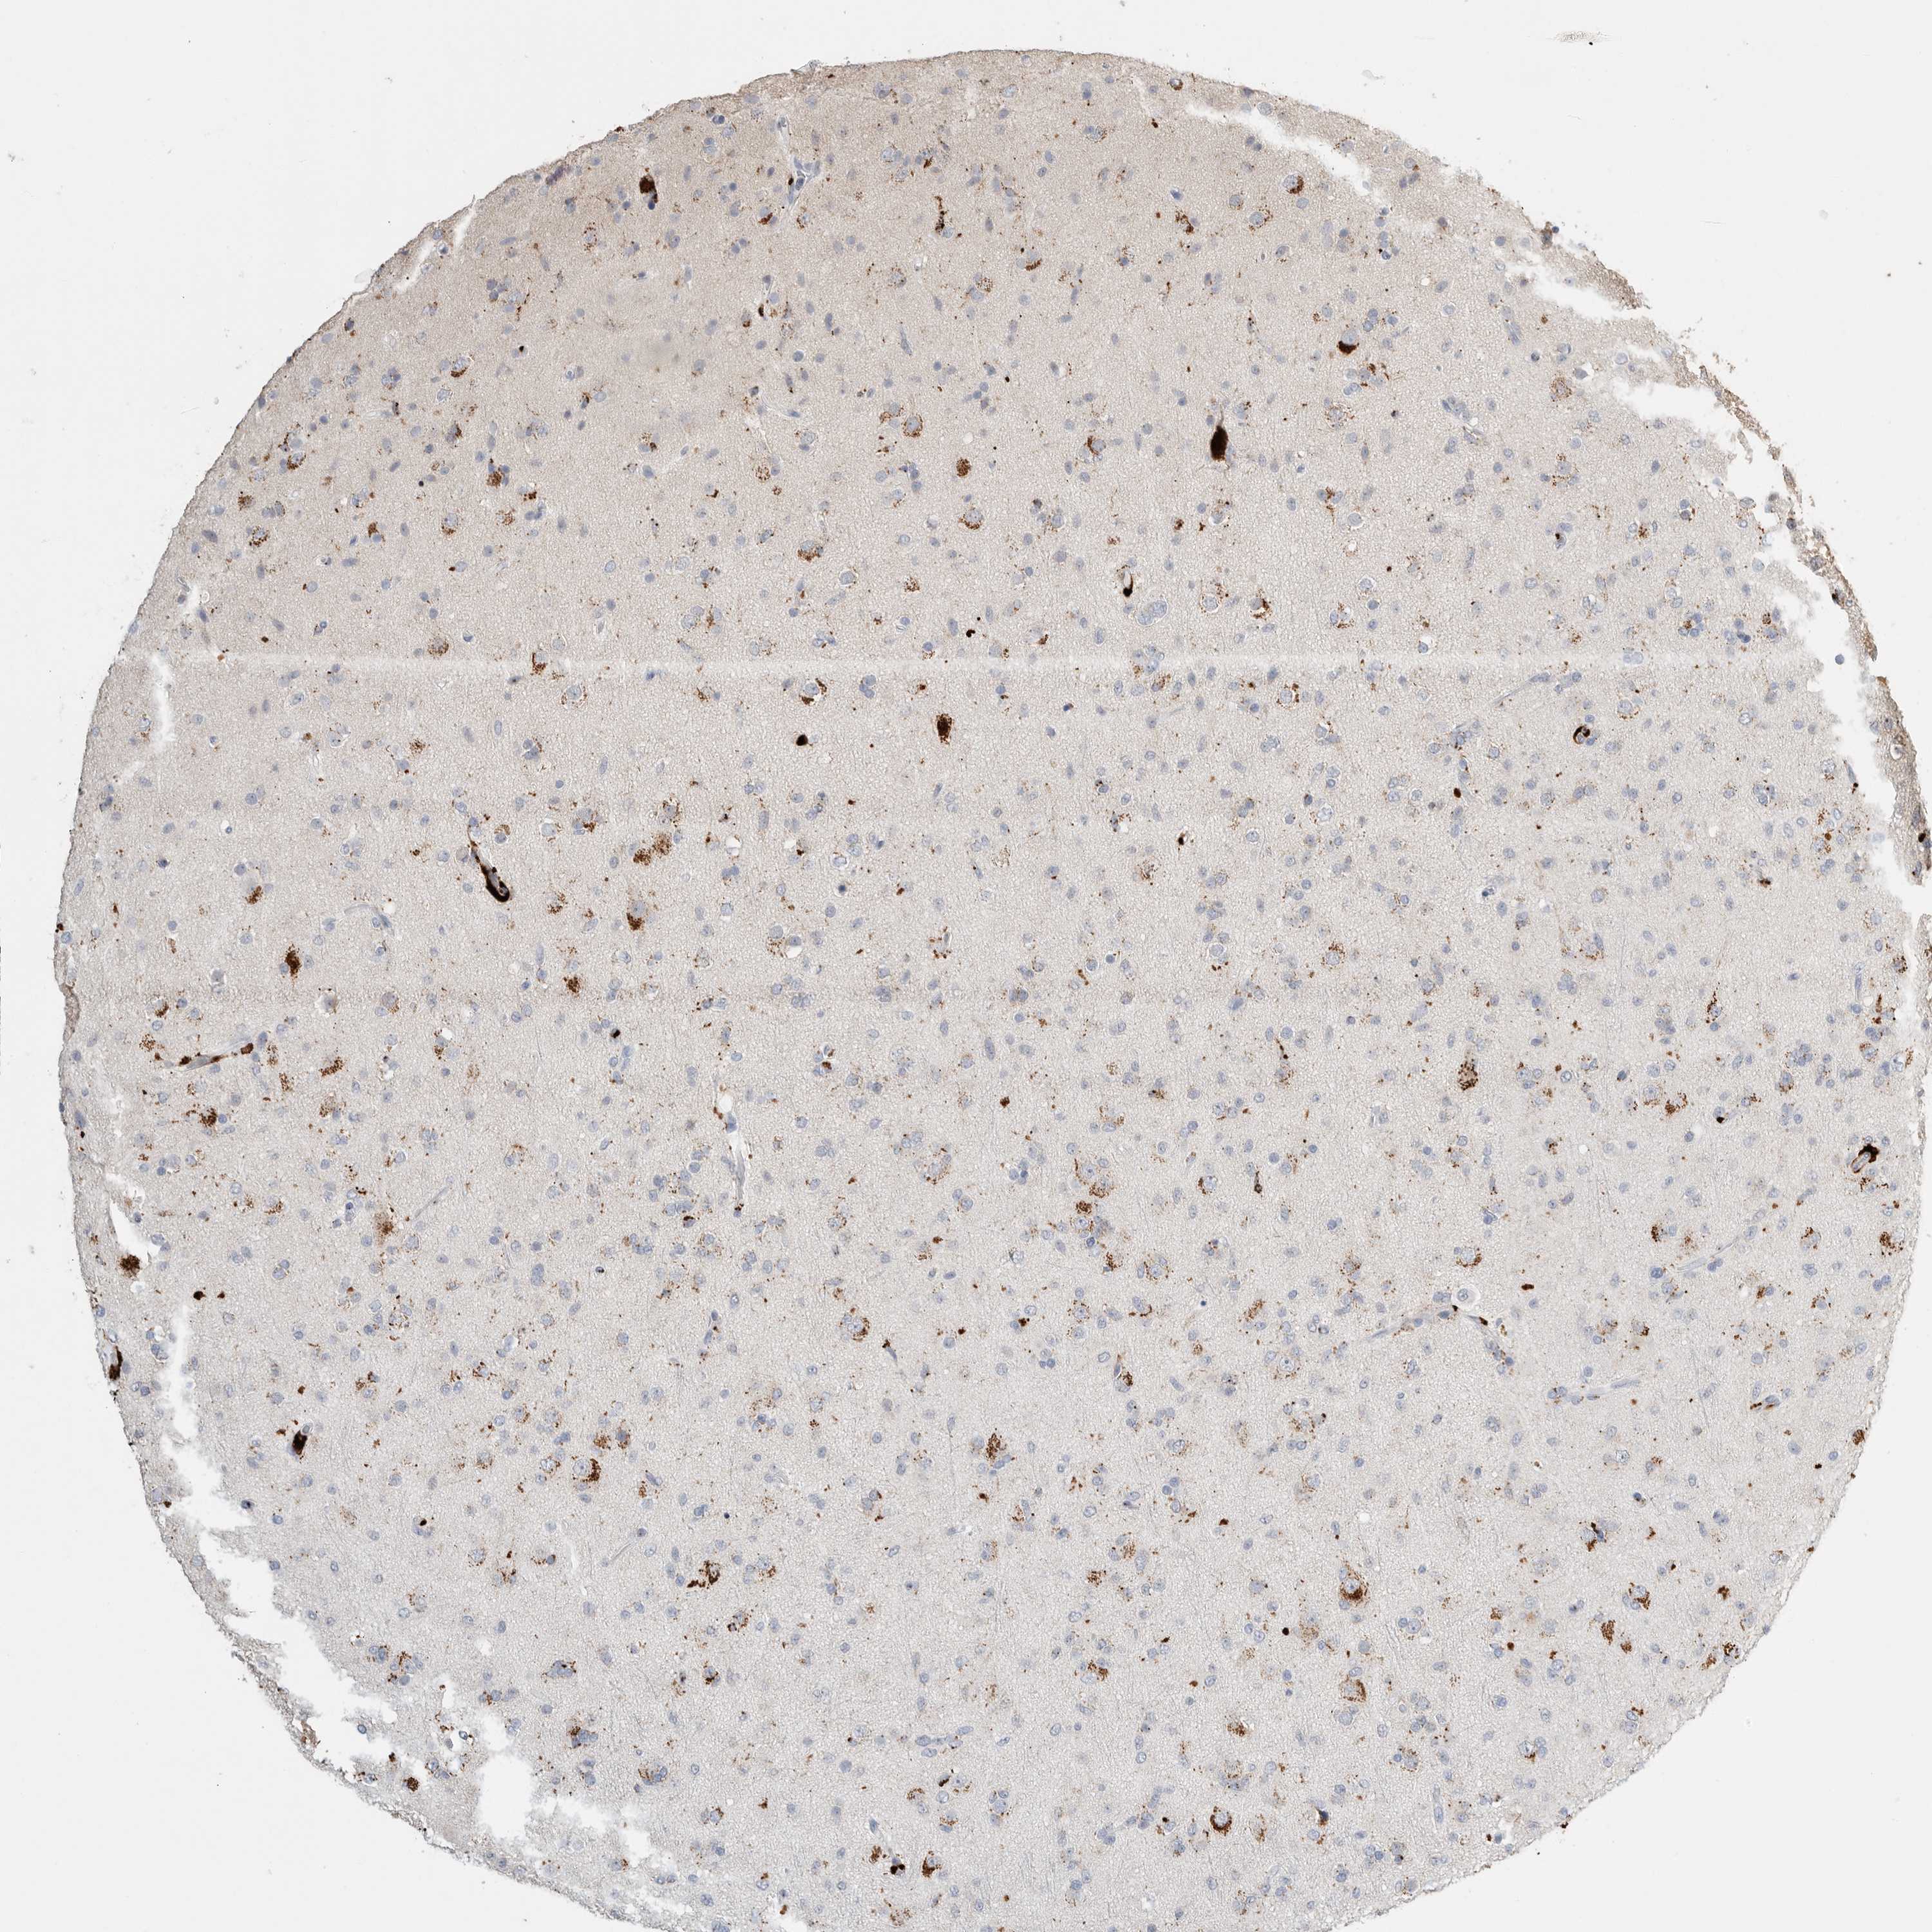

GLIOMA - Protein expressioni

A mouse-over function shows sample information and annotation data. Click on an image to view it in a full screen mode. Samples can be filtered based on level of antibody staining by selecting one or several of the following categories: high, medium, low and not detected. The assay and annotation is described here.

Note that samples used for immunohistochemistry by the Human Protein Atlas do not correspond to samples in the TCGA dataset.

Antibody stainingi

Antibody staining in the annotated cell types in the current human tissue is reported as not detected, low, medium, or high, based on conventional immunohistochemistry profiling in selected tissues. This score is based on the combination of the staining intensity and fraction of stained cells.

Each image is clickable and will lead to virtual microscopy that enables deeper exploration of all samples and also displays staining intensity scores, fraction scores and subcellular localization as well as patient and tissue information for each sample.

Antibody HPA025226

Antibody CAB019296

Glioma, malignant, High grade

Glioma, malignant, Low grade